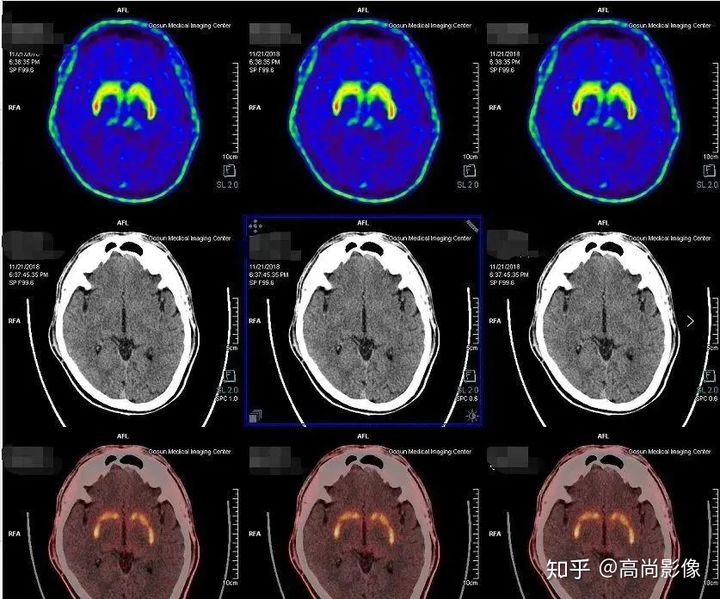

雙側(cè)尾狀核、殼核多巴胺轉(zhuǎn)運體分布對稱、均勻

相比之下,童大媽就沒有這么幸運了。除了右邊身子總是抖動,童大媽還有嗅覺障礙、動作緩慢等癥狀。童大媽的PET/CT檢查結(jié)果符合帕金森的表現(xiàn),為臨床診斷提供了重要依據(jù)。

雙側(cè)尾狀核多巴胺轉(zhuǎn)運體分布對稱,左側(cè)殼核后部多巴胺轉(zhuǎn)運體分布較對側(cè)明顯減少,結(jié)合童大媽癥狀,先考慮帕金森。